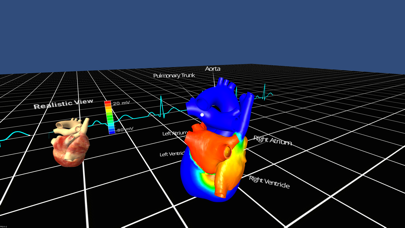

Скриншоты